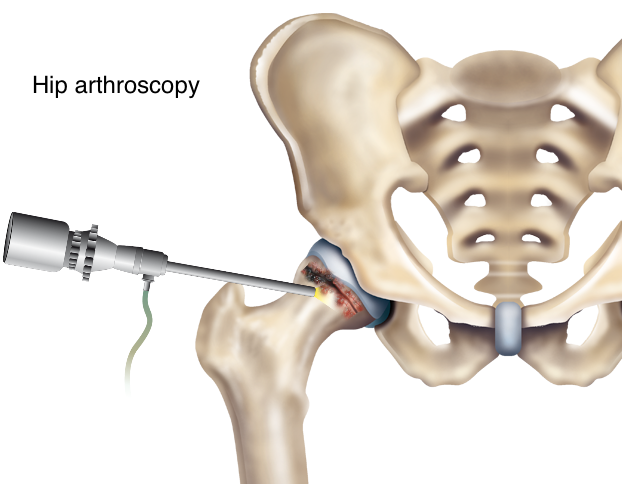

Замена таз сустава

Замена таз сустава 113 фотографий